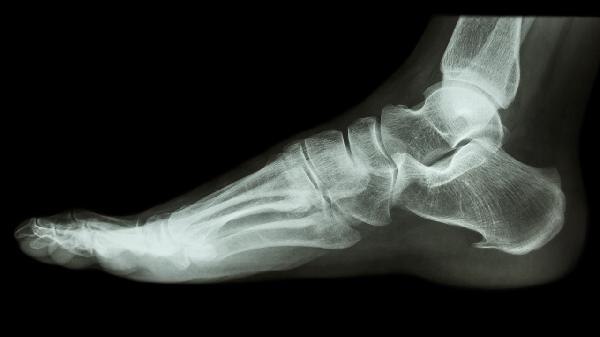

日常应避免足部过度负重活动,坚持热水泡脚促进血液循环。补钙和维生素D有助于骨骼健康,但需注意过量补充可能加速异位钙化。若出现持续夜间痛或晨僵,需排查是否合并跟腱炎或足底筋膜炎。建议选择透气性好的运动鞋,运动前后做好足部拉伸,中老年人群可定期进行足部X线检查。出现行走困难或畸形时需及时至足踝外科就诊。